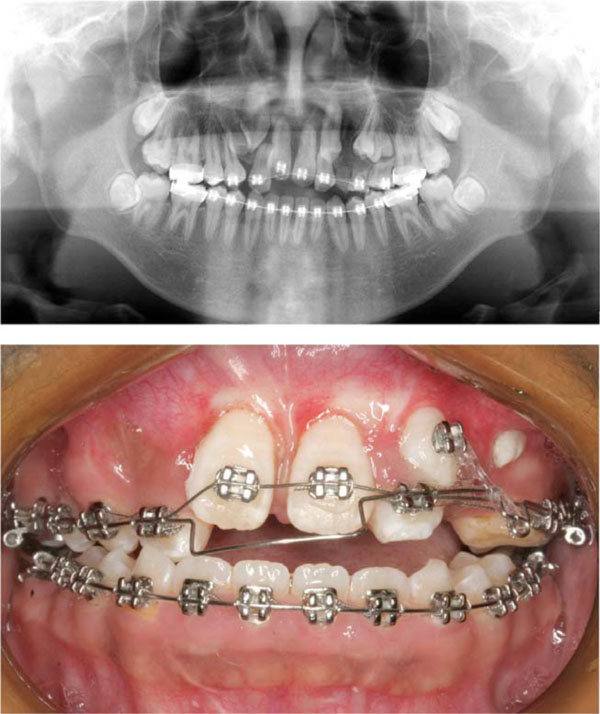

Mid-treatment intraoral photo and radiograph.

After extraction of all the supernumerary and lower deciduous teeth, the 0.022Х0.028 in slot straight-wire fixed appliance was used to level maxillary and mandible teeth. Once the upper teeth were aligned (for 6 months with 0.012, 0.014 and 0.016 NITI wire) and space recovered for the impacted central incisors by means of the nitinol spring (for 6 months with 0.5 mm stainless steal wire), surgery assisted traction for central incisor was performed individually. In brief, the labial surface of the maxillary central incisor was surgically exposed. An attachment was then bonded to the teeth surface and the flap fully sutured back to the former position. The twisted stainless steel ligature wire (0.2 mm) that has been previously placed in the attachment was then drawn occlusally with the main archwire of 0.5 mm stainless steel wire. Ten months later, both central incisors erupted into the oral cavity, the brackets were banded and proper guidance was provided to the central incisors during normal eruption. In order to create space for the impacted upper canines and premolars, bilateral upper lateral incisors with severe root resorption and retained primary teeth were extracted. Then, surgery assisted eruption guidence for impacted canines and premolars were performed individually. The main archwire of 0.5 mm stainless steel wire with loop was placed, the power chain was connected between impacted canine and the loop. Four months later, the canine was guided into the upper arch (Fig. 2). After 10 months of alignment of all the dentition (with 0.016, 0.016x0.022, 0.017x0.025, 0.018x0.025NITI wire), .018x.025 stainless steel wire was placed. In this stage, all the impacted teeth were guided to normal position, the patient and parents were satisfied with the teeth but disliked the concave face (Fig. 3). Hence, the patient was suggested to receive surgery. The bimaxillary orthognathic approach including Lefort I osteotomy. Bilateral sagittal split ramus osteotomy (BSSRO) and genioplasty was performed to correct skeletal problem. Titanium screws were used for rigid fixation. Maxillomandibular fixation with an occlusal splint was performed for 4 weeks. The MEAW technology (0.018x0.025 stainless steel wire) together with vertical elastic and short class III elastic was performed to establish the ideal occlusal relationship. After 8 months of post-surgical orthodontic treatment, Ideal occlusion was achieved and the fixed appliance was removed. Clear retainers were worn in both jaws. The retainers were maintained all day for 6 months, subsequently, were worn only during the night for another 1 year. Total active treatment period lasted for 5 years including 1 year missing for operation fee preparation.